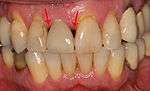

Long term

The long-term complications that result from restoring teeth with implants relate, directly, to the risk factors of the patient and the technology. There are the risks associated with esthetics including a high smile line, poor gingival quality and missing papillae, difficulty in matching the form of natural teeth that may have unequal points of contact or uncommon shapes, bone that is missing, atrophied or otherwise shaped in an unsuitable manner, unrealistic expectations of the patient or poor oral hygiene. The risks can be related to biomechanical factors, where the geometry of the implants does not support the teeth in the same way the natural teeth did such as when there are cantilevered extensions, fewer implants than roots or teeth that are longer than the implants that support them (a poor crown-to-root ratio). Similarly, grinding of the teeth, lack of bone or low diameter implants increase the biomechanical risk. Finally there are technological risks, where the implants themselves can fail due to fracture or a loss of retention to the teeth they are intended to support.[39](pp27–51)

From these theoretical risks, derive the real world complications. Long-term failures are due to either loss of bone around the tooth and/or gingiva due to peri-implantitis or a mechanical failure of the implant. Because there is no dental enamel on an implant, it does not fail due to cavities like natural teeth. While large-scale, long-term studies are scarce, several systematic reviews estimate the long-term (five to ten years) survival of dental implants at 93–98 percent depending on their clinical use.[1][2][3] During initial development of implant retained teeth, all crowns were attached to the teeth with screws, but more recent advancements have allowed placement of crowns on the abutments with dental cement (akin to placing a crown on a tooth). This has created the potential for cement, that escapes from under the crown during cementation to get caught in the gingiva and create a peri-implantitis (see picture below). While the complication can occur, there does not appear to be any additional peri-implantitis in cement-retained crowns compared to screw-retained crowns overall.[40] In compound implants (two stage implants), between the actual implant and the superstructure (abutment) are gaps and cavities into which bacteria can penetrate from the oral cavity. Later these bacteria will return into the adjacent tissue and can cause periimplantitis. As prophylaxis these implant interior spaces should be sealed.[41]

Criteria for the success of the implant supported dental prosthetic varies from study to study, but can be broadly classified into failures due to the implant, soft tissues or prosthetic components or a lack of satisfaction on the part of the patient. The most commonly cited criteria for success are function of at least five years in the absence of pain, mobility, radiographic lucency and peri-implant bone loss of greater than 1.5 mm on the implant, the lack of suppuration or bleeding in the soft tissues and occurrence of technical complications/prosthetic maintenance, adequate function, and esthetics in the prosthetic. In addition, the patient should ideally be free of pain, paraesthesia, able to chew and taste and be pleased with the esthetics.[37]